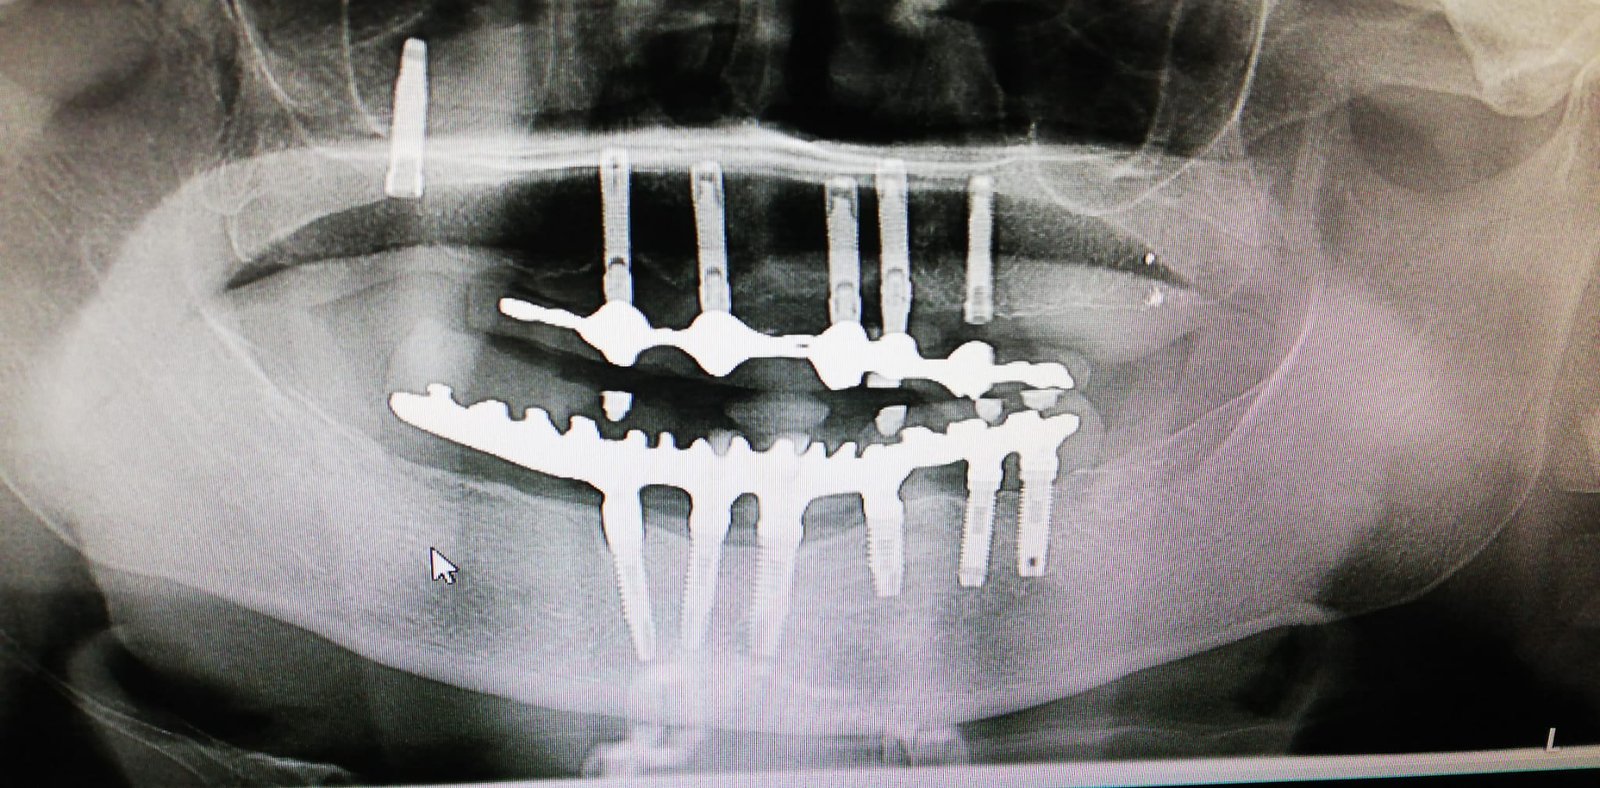

Paciente mujer fumadora de 10 cigarrillos al día, presenta movilidad de rehabilitación superior total con laminas de Linkow bilateral. El tratamiento fue realizado hace 30 años; presenta fistula en palatino. [...]

Buenas tardes. Me gustaría saber si me pueden ayudar a saber cuales son los implantes que tiene mi paciente, para así poder comprar los aditamentos. Muchas gracias de antemano por [...]